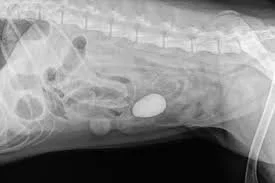

gi foreign body dog

• abdominal radiographs (X-rays)

Radiographs often help identify the presence and location of the obstruction.